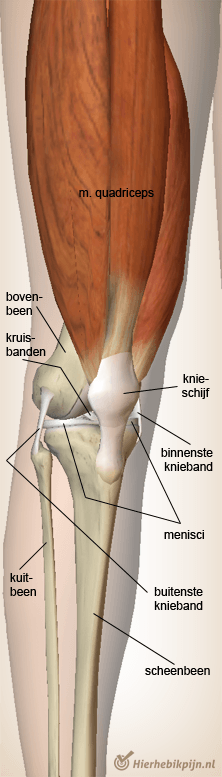

Knie